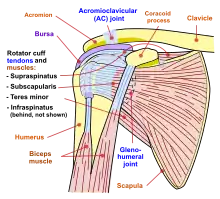

| Shoulder joint | |

Shoulder impingement syndrome is a syndrome involving tendonitis (inflammation of tendons) of the rotator cuff muscles as they pass through the subacromial space, the passage beneath the acromion. It is particularly associated with tendonitis of the supraspinatus muscle.[1] This can result in pain, weakness, and loss of movement at the shoulder.[2][3]

When the arm is raised, the subacromial space (gap between the anterior edge of the acromion and the head of the humerus) narrows; the supraspinatus muscle tendon passes through this space.[6] Anything that causes further narrowing has the tendency to impinge the tendon and cause an inflammatory response, resulting in impingement syndrome. Such causes can be bony structures such as subacromial spurs (bony projections from the acromion), osteoarthritic spurs on the acromioclavicular joint, and variations in the shape of the acromion. Thickening or calcification of the coracoacromial ligament can also cause impingement. Loss of function of the rotator cuff muscles, due to injury or loss of strength, may cause the humerus to move superiorly, resulting in impingement. Inflammation and subsequent thickening of the subacromial bursa may also cause impingement.[2]

The scapula plays an important role in shoulder impingement syndrome.[8] It is a wide, flat bone lying on the posterior thoracic wall that provides an attachment for three different groups of muscles. The intrinsic muscles of the scapula include the muscles of the rotator cuff- the subscapularis, infraspinatus, teres minor and supraspinatus.[9] These muscles attach to the surface of the scapula and are responsible for the internal and external rotation of the glenohumeral joint, along with humeral abduction. The extrinsic muscles include the biceps, triceps, and deltoid muscles and attach to the coracoid process and supraglenoid tubercle of the scapula, infraglenoid tubercle of the scapula, and spine of the scapula. These muscles are responsible for several actions of the glenohumeral joint. The third group, which is mainly responsible for stabilization and rotation of the scapula, consists of the trapezius, serratus anterior, levator scapulae, and rhomboid muscles and attach to the medial, superior, and inferior borders of the scapula. Each of these muscles has its own role in shoulder function and must be in balance with the others in order to avoid shoulder pathology.